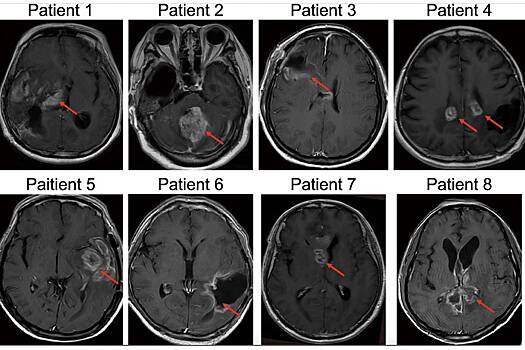

В ходе испытаний восемь пациентов с рецидивом глиобластомы, вернувшихся после операции, получили одну из трех доз вируса Ad-TD-nsIL12. Этот вирус создан на основе аденовируса, который обычно вызывает простудные заболевания, но был модифицирован для локальной доставки IL-12 — мощного иммуностимулирующего белка — непосредственно к области опухоли.

В результате удалось определить максимальную дозу, при которой лечение оставалось безопасным и хорошо переносилось пациентами. Наблюдались побочные эффекты лишь легкой или средней тяжести, что подтверждает возможность дальнейших испытаний на более широком круге пациентов. Одному пациенту удалось достичь полной ремиссии опухоли, у другого наблюдалось значительное уменьшение размеров опухоли.